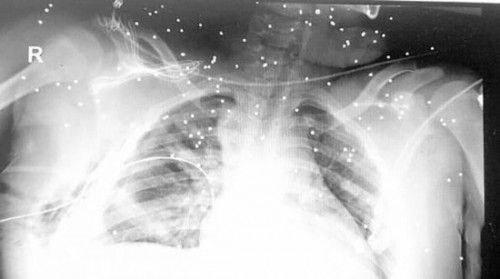

مرآة البحرين: قال المواطن حسن العجمي إن الوضع الصحي العام لابن أخته الطفل محمد السواد (13 عاماً) قد استقر أمس الاثنين 2 فبراير/ شباط إلا أن هناك قلق كبير بوجود احتمالية من فقدانه لإحدى عينيه بعد أن وصلت شظايا "الشوزن" لها، وما يزيد قلق العائلة هو عدم إعطائهم أي تقارير طبية أو تشخيصية بخصوص إصابة العين، مشيراً إلى أن النيابة العامة قامت باستدعائه مع والد الطفل أمس وذلك للاستماع لأقوالهما بشأن الواقعة.

يذكر أن الطفل محمد السواد هو لأب من سترة وأم من الدراز، وقد أصيب يوم الجمعة 30 يناير/ كانون الثاني 2014 برصاص "الشوزن" حينما صادف وجوده بالقرب من بيت جده مع خروج مسيرة سلمية حاشدة للمطالبة بإطلاق سراح الشيخ علي سلمان، وهي ما ردت عليها قوات الأمن بالقمع المفرط مستخدمة الغازات المسيلة للدموع والرصاص الانشطاري الذي أصاب الطفل.